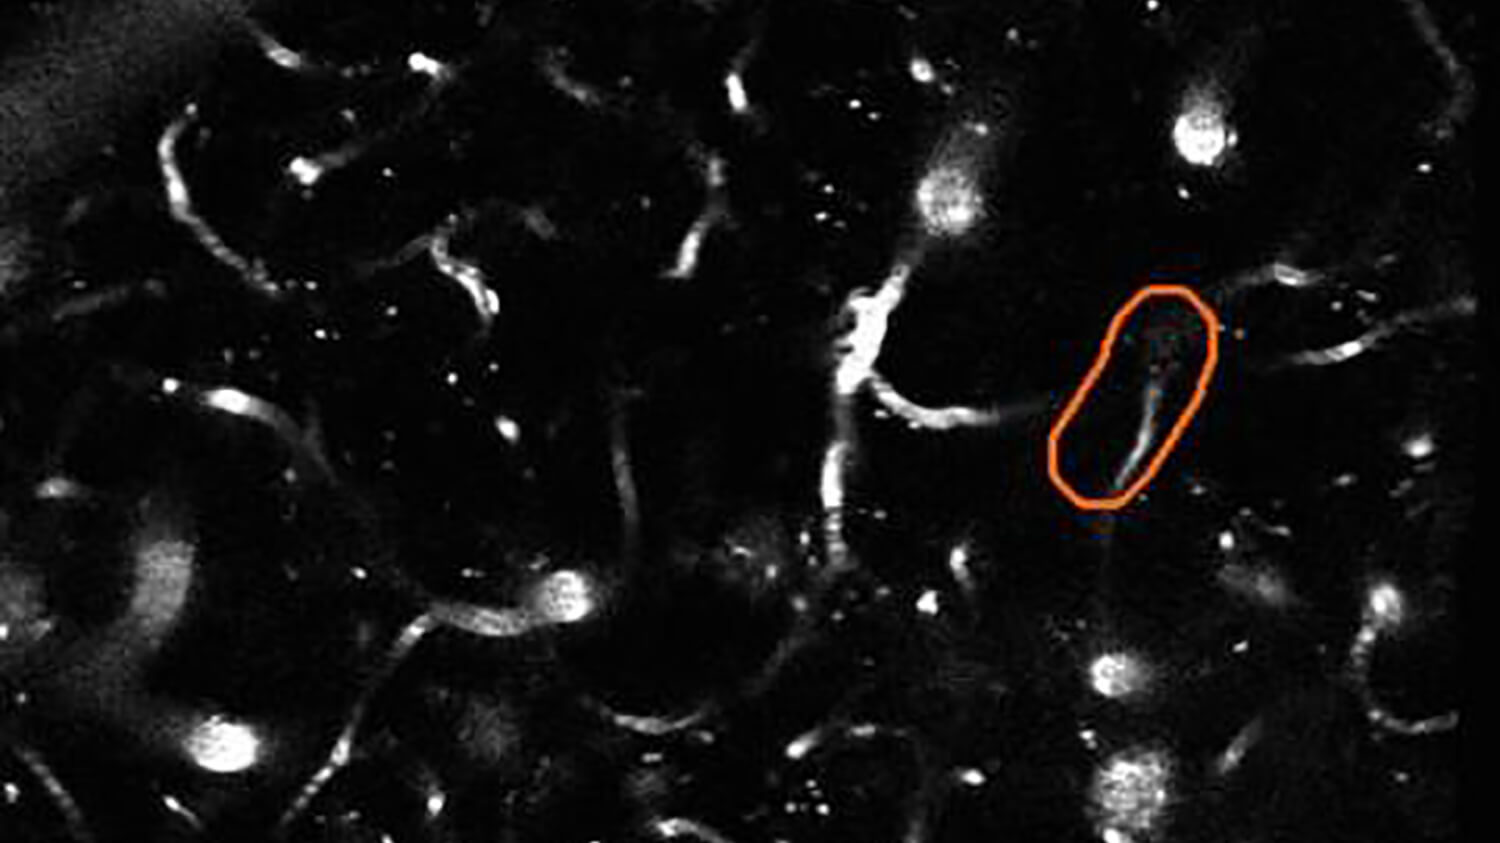

Cornell University researchers have made breakthrough discoveries in understanding the role of brain blood flow in Alzheimer’s disease (AD), but more evidence is needed to establish whether freeing stalled capillaries might results in a possible treatment approach. The problem is that it takes an entire year to analyze the data needed to answer each research question, and progress to date has been very slow. “Stall Catchers” is a citizen science research project developed by the Human Computation Institute in collaboration with Cornell investigators Chris Schaffer and Nozomi Nishimura aimed at speeding up Cornell’s data analysis by turning it into an online game that anyone can play. Our Phase I goal is to see whether thousands of public participants can analyze the research data just as accurately as lab experts, but by working together, do it much faster. In Phase II, we will apply the validated crowd engine to new experimental data to see if we can reduce the time to a treatment target from decades to just a few years. This is the first citizen science project supporting Alzheimer’s disease (AD) research. To learn more about EyesOnAlz, visit www.eyesonalz.com.